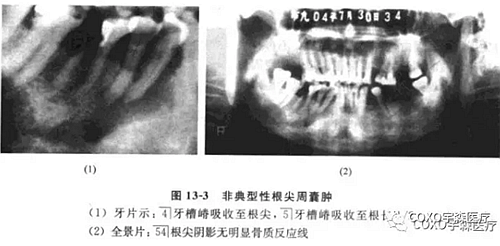

(二)非典型性根尖周囊腫根尖周囊腫的診斷除臨床癥狀外,主要靠X線片檢查。經(jīng)典的診斷標準應為在相應患牙的根尖部呈現(xiàn)界限清楚的圓形骨質(zhì)稀疏的透射陰影。

周邊可有不同程度白色骨質(zhì)反應線;但是不應忽略有時根尖部 線區(qū)表現(xiàn)可以呈非典型性。

病例:女性,72歲,右下牙齦腫脹3周,有牙痛史,外院拍片診斷為“根尖周囊腫”并行頰側(cè)組織切片檢查,病理診斷為“炎癥性病變”轉(zhuǎn)來我院。

檢查:54]頰側(cè)骨膨隆,頰側(cè)活檢切口無膿性分泌,54]無松動,無叩痛,6]殘冠、x線片示:654]]冠部均有充填物,4]牙槽骨吸收已近根尖,51]牙槽骨吸收至根長1/2。全景片示:54]根尖陰影,無明顯骨質(zhì)反應線(圖13-3),54]電活力測試無反應。

局麻下拔除654],見根尖部有大量肉芽組織予以刮除,術后傷口順利愈合。病理報告:右下后牙區(qū)根尖周囊腫,伴反應性骨質(zhì)增生。

分析與評述

本病例的臨床診斷為根尖周囊腫,似無太大疑問,但X線表現(xiàn)則十分不典型:54]根尖骨質(zhì)呈不規(guī)則、潛穴性吸收,底部幾達顏孔,更無明顯骨質(zhì)反應線。由于54]無明顯松動及叩痛,加之頰側(cè)骨質(zhì)膨脹,致使牙體牙髓病醫(yī)師疑為腫瘤,不敢進行根管治療術。手術結(jié)果證實仍為根尖周囊腫伴反應性骨質(zhì)增生。結(jié)合術中見病灶區(qū)有大量肉芽組織,說明本病例的炎癥過程可能持續(xù)時間較長,程度較重,致使 線片表現(xiàn)呈不典型性。本例的經(jīng)驗是:應牢記根尖周囊腫還有不典型表現(xiàn)者,臨床應綜合各方面的因素考慮,方能更進一步提高臨床診斷水平。